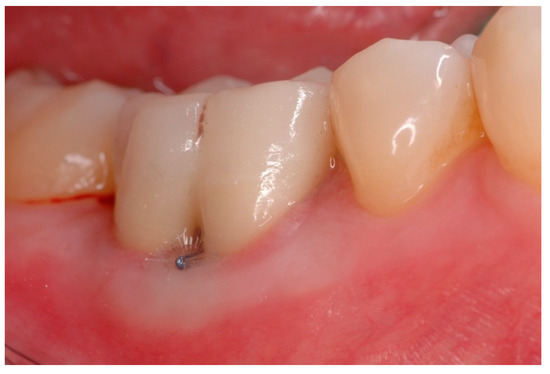

Figure 7. Exposed furcation lesion—Class I (EI): (a) First mandibular molar; (b) Buccal furcation lesion with horizontal attachment loss of 1 mm.